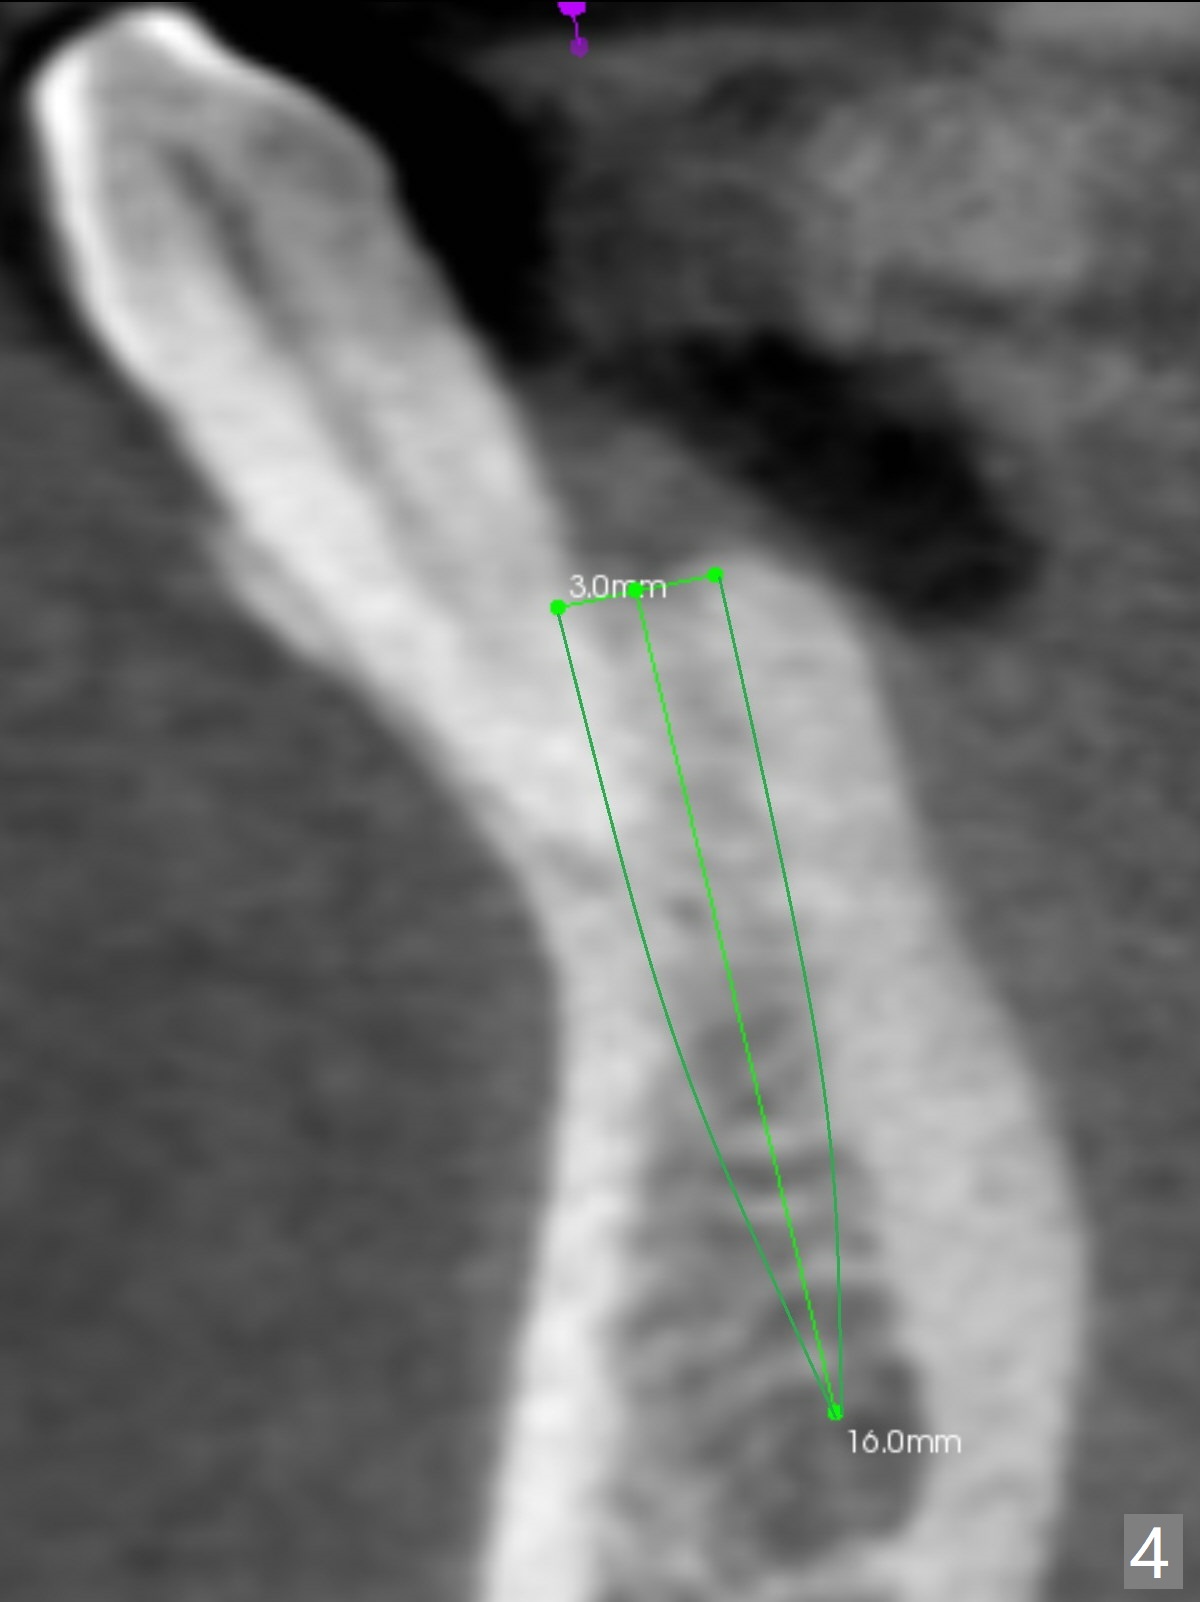

A 44-year-old woman will return for #22/23 (fusion) extraction and implant 2.5 months after one at #25 (Fig.1). If the mesiodistal width of the extraction socket(s) is not particularly wide, one implant will be placed. The tooth #22 seems to be buccally positioned (Fig.2 B). After extraction (Fig.3 black area), initiate osteotomy lingually (red line). Since the spongy bone is not wide buccolingually, a 3 mm implant appears to be appropriate (Fig.4).